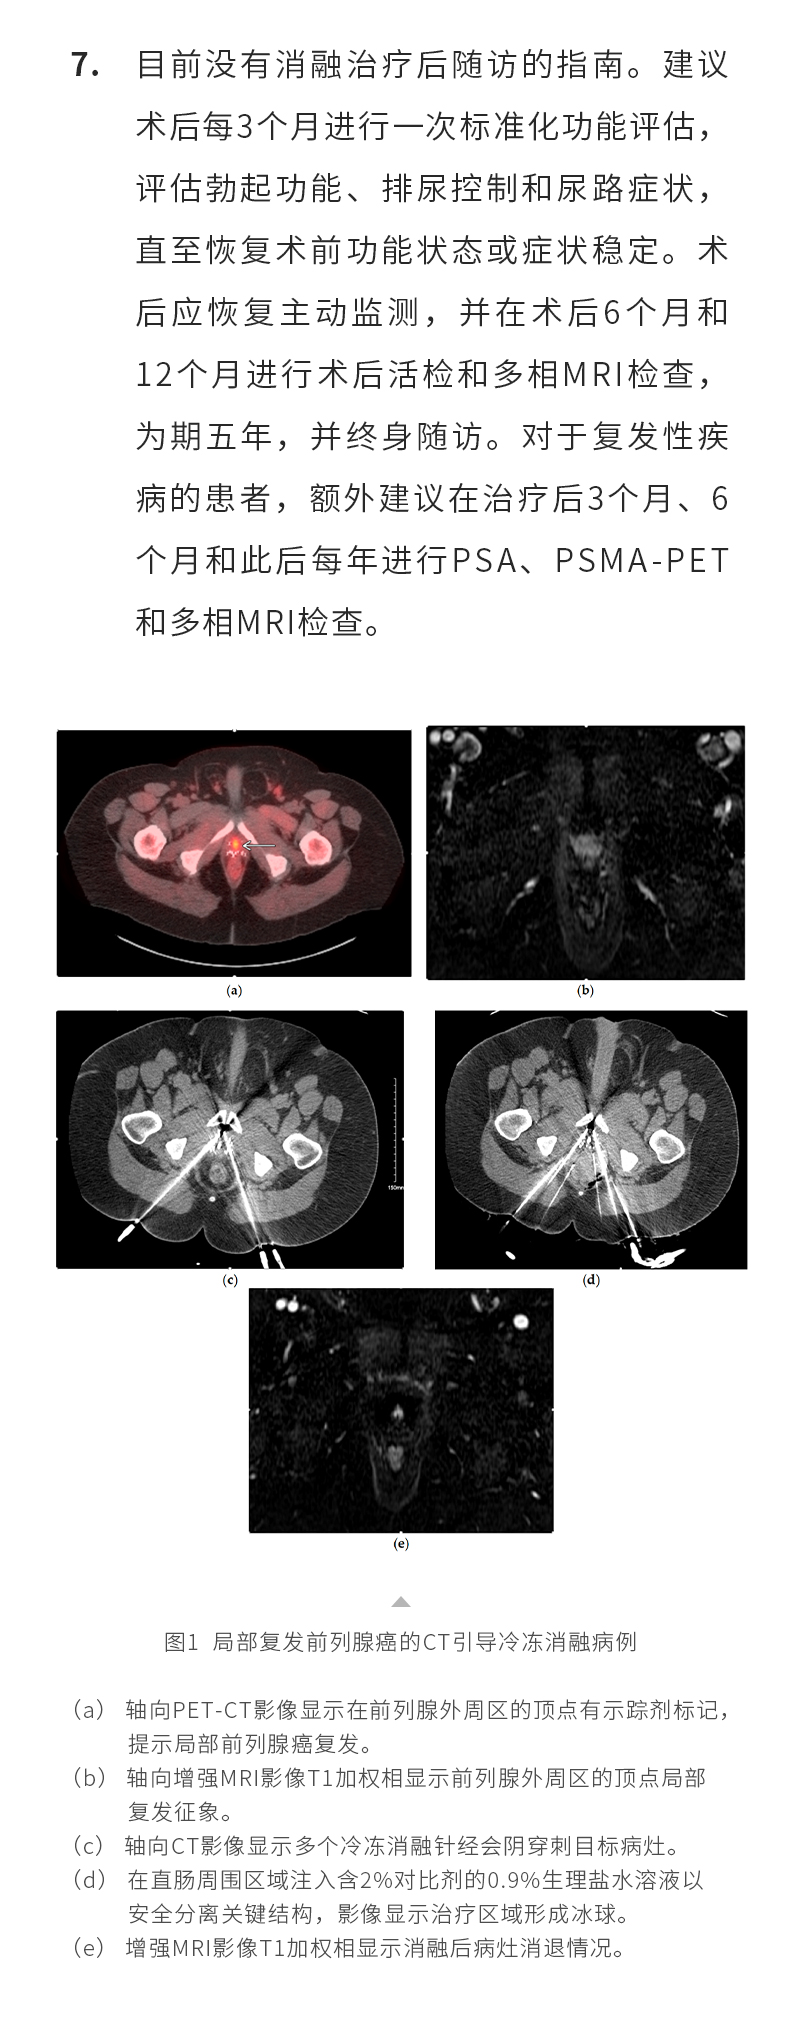

日本特黄特色a大片免费高清观看视频_亚洲午夜综合_一女被两男3p做爰视频_丰满少妇久久_欧美激情在线第一页_久久五月激情_亚洲成人激情在线_滚床单又黄又肉细节描写_日韩av综合在线观看_人妖一级片